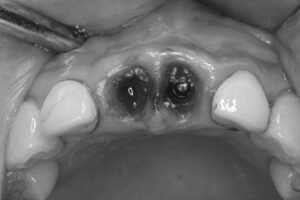

インプラント埋入

抜歯直後の骨に対し、精密な位置決めを行いながらインプラントを埋入します。十分な初期固定が得られたため、この症例では即時荷重が可能と判断しました。